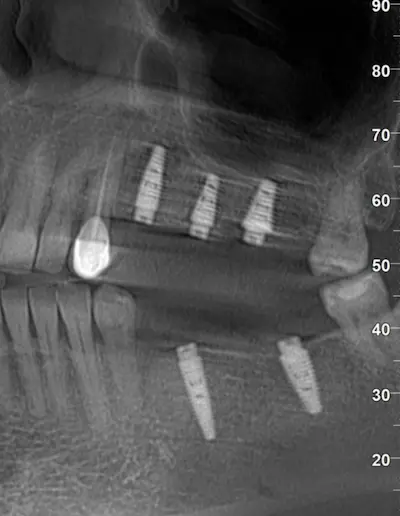

Сканы КТ имплантации зубов, 2026-04-18

Скан КТ, 2026-04-18

Сканы КТ имплантации зубов, 2026-04-18

Скан КТ имплантации зубов, 2026-04-17

Сканы КТ имплантации зубов, 2026-04-18

KT: имплантация зубов DentalKnysh, 2025-01-03, сканы

KT: имплантация зубов DentalKnysh, 2025-01-03, сканы

KT: имплантация зубов DentalKnysh, 2025-01-03, сканы

КТ имплантации зубов в DentalKnysh (10 имплантов), 2023-11-03

С 2023-09-05 по 2023-09-09 сканы КТ от 6 до 12 имплантов в DentalKnysh (4 фото):

Синуслифтинг и имплантация зубов, 6 имплантов, all-on-6, КТ скан 1, 2023-08-31

Фото отчет Имплантация зубов, 6 имплантов, КТ скан 3, 2023-08-31

Фото отчет Имплантация зубов, 8 имплантов, all-on-4, КТ скан 1, 2023-08-31